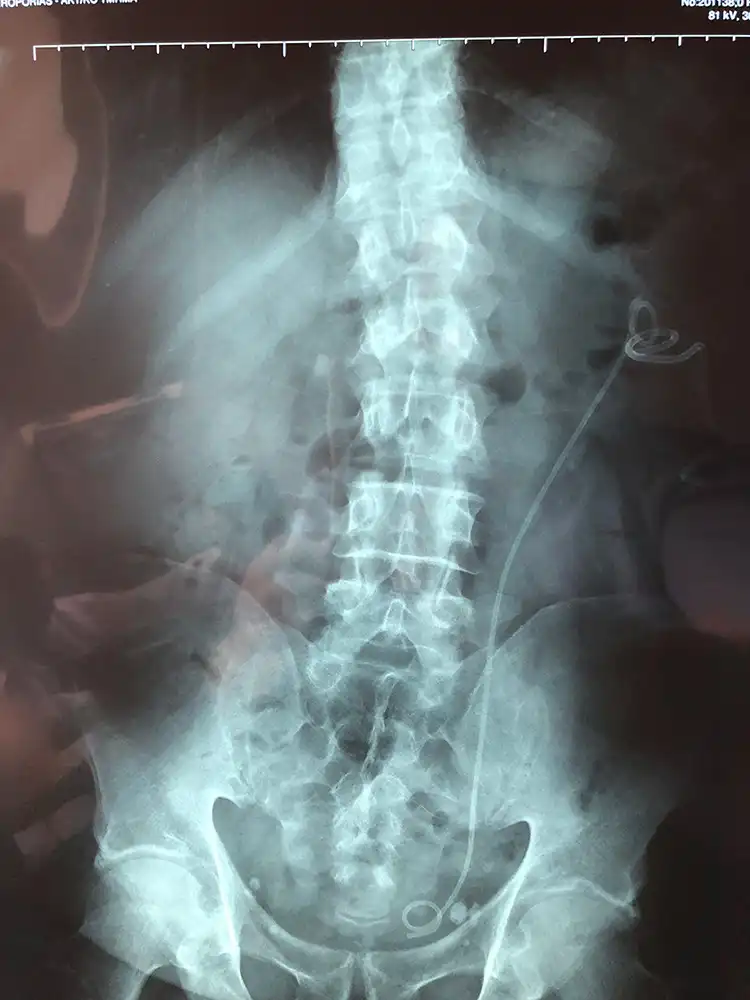

Ασθενής με ευμεγέθη λίθο της νεφρικής πυέλου αντιμετωπίστηκε με διαδερμική νεφρολιθοθρυψία. Η πρώτη φωτογραφία είναι προεγχειρητικά ενώ η δεύτερη είναι την 1η ημέρα μετεγχειρητικά.